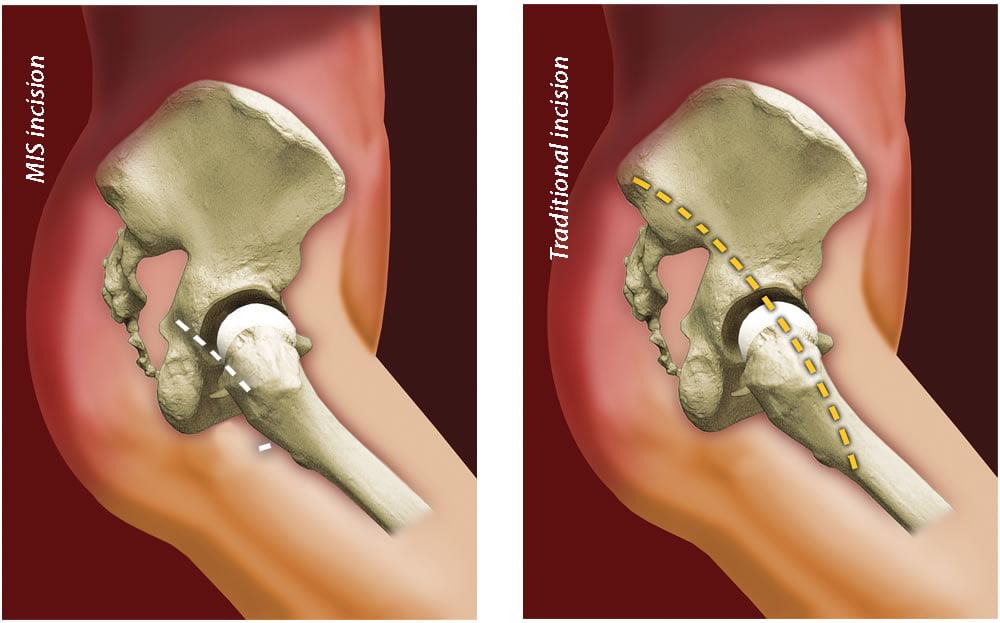

Раздел: Необычные решения